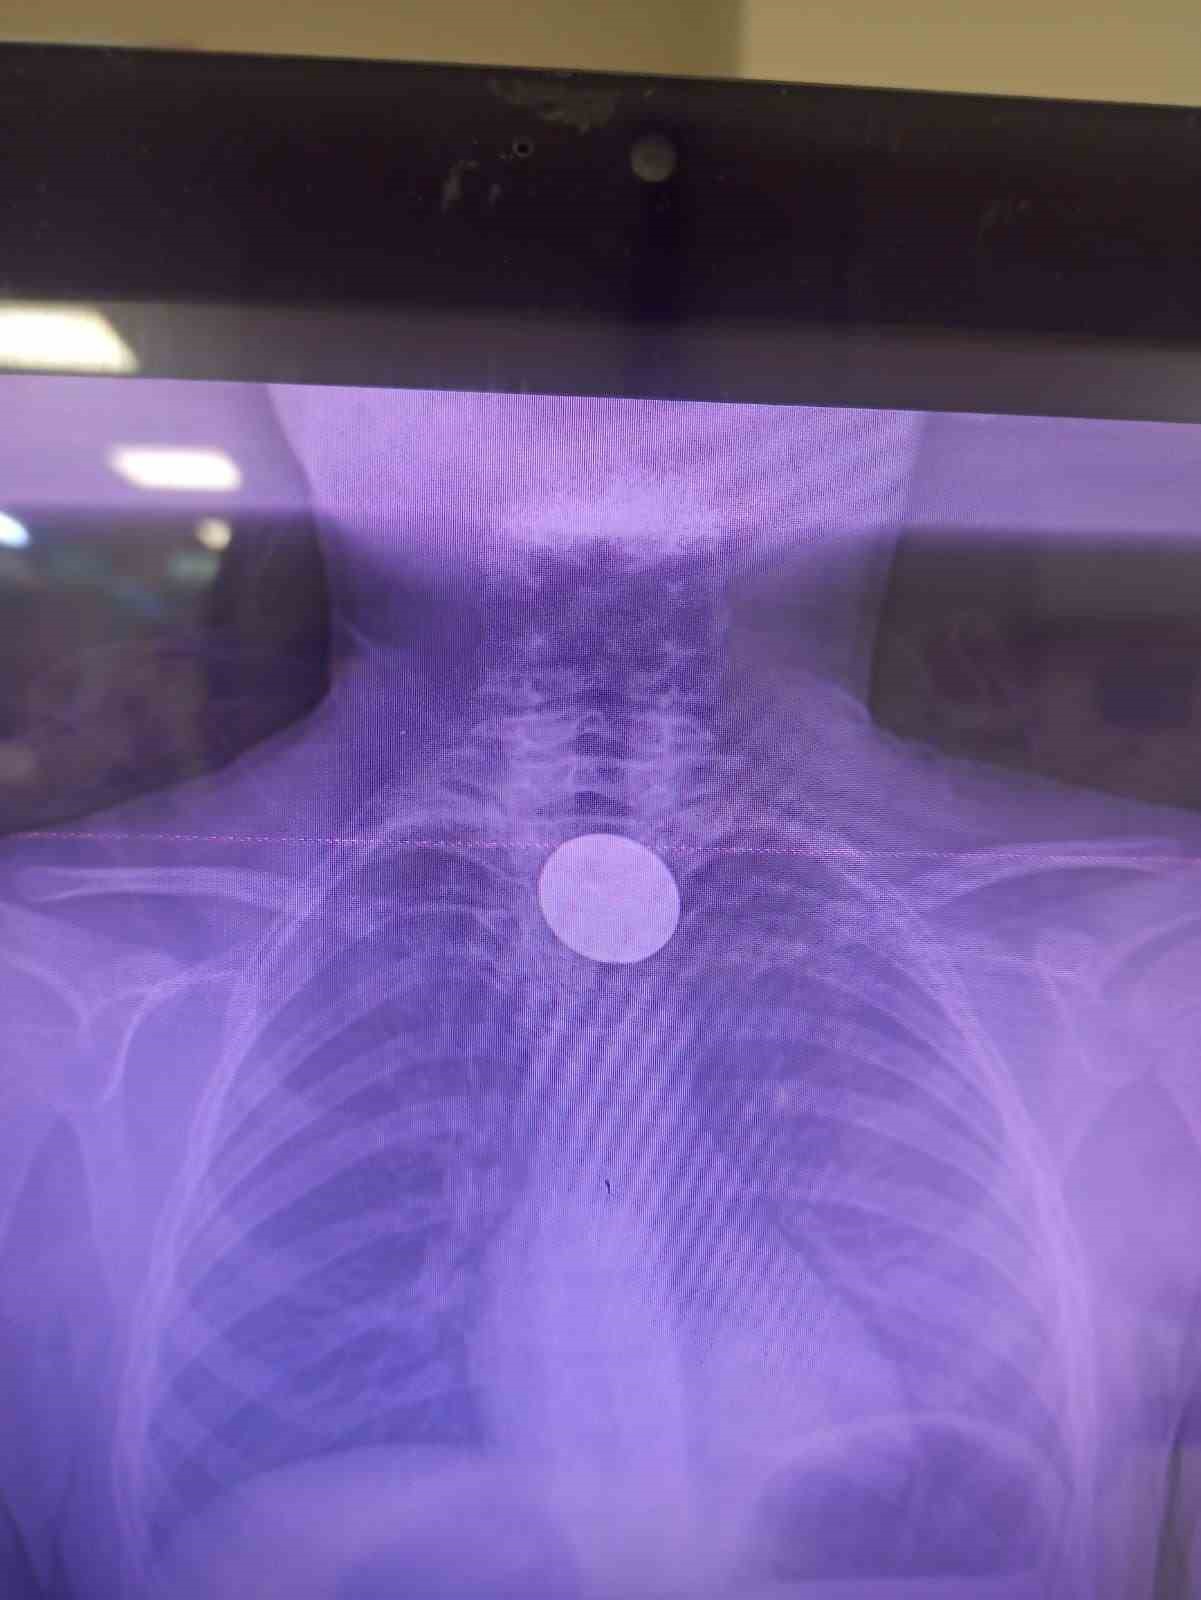

Yabancı cisim yutma şikayetiyle ailesi tarafından Siirt Eğitim ve Araştırma Hastanesine getirilen 8 yaşındaki Y.K., yapılan ilk değerlendirme ve görüntüleme tetkiklerinin ardından ilgili branşlarca operasyona alındı. Y.K.’nın yemek borusuna kadar ilerlediği tespit edilen madeni para, gastroenteroloji uzmanı Dr. Yaren Dirik ve kulak burun boğaz hekimi Yasin Gökçınar tarafından müdahale edilerek çıkartıldı. Operasyonun ardından bir süre gözlem altında tutulan Y.K., tedavisinin tamamlanmasıyla taburcu edildi.

Siirt Eğitim ve Araştırma Hastanesi Başhekim Yardımcısı Uzman Dr. Burak Özkan, çocuk hastalarda yabancı cisim yutma vakalarının ciddi riskler oluşturabileceğini söyledi. Uzm. Dr. Özkan, "Hastanemize başvuran 8 yaşındaki hastamızın yemek borusuna kaçan madeni para, gastroenteroloji ve KBB ekiplerimizin koordineli ve titiz çalışmasıyla herhangi bir komplikasyona yol açmadan başarılı bir şekilde çıkarılmıştır. Operasyon süreci sorunsuz geçmiş olup hastamızın genel durumu iyidir" dedi.